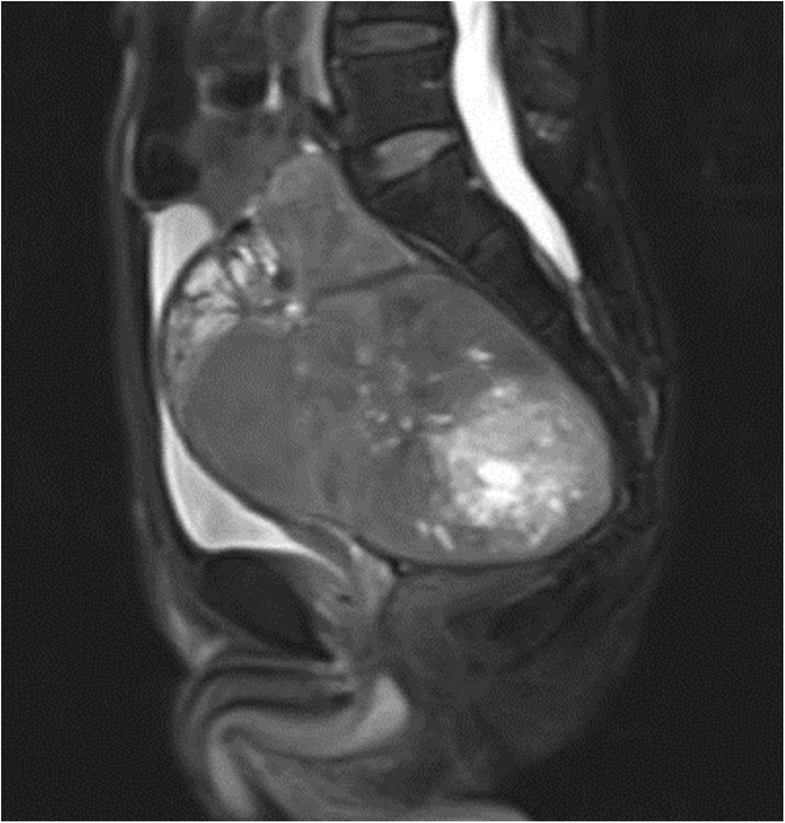

A giant pelvic solitary fibrous tumor with DoegePotter syndrome Doege Potter Syndrome The most common location was the pleural cavity (left 12 cases and right 28 cases). The tumors originated from the pleural cavity, lung, pelvis, liver, retroperitoneum, kidney, mediastinal, the sella, uterus, bladder, intestine, mandibular, and the thigh. Moreover, 28/71 (39.4%) were benign and 43/71 (60.6%) were. Doege Potter Syndrome.